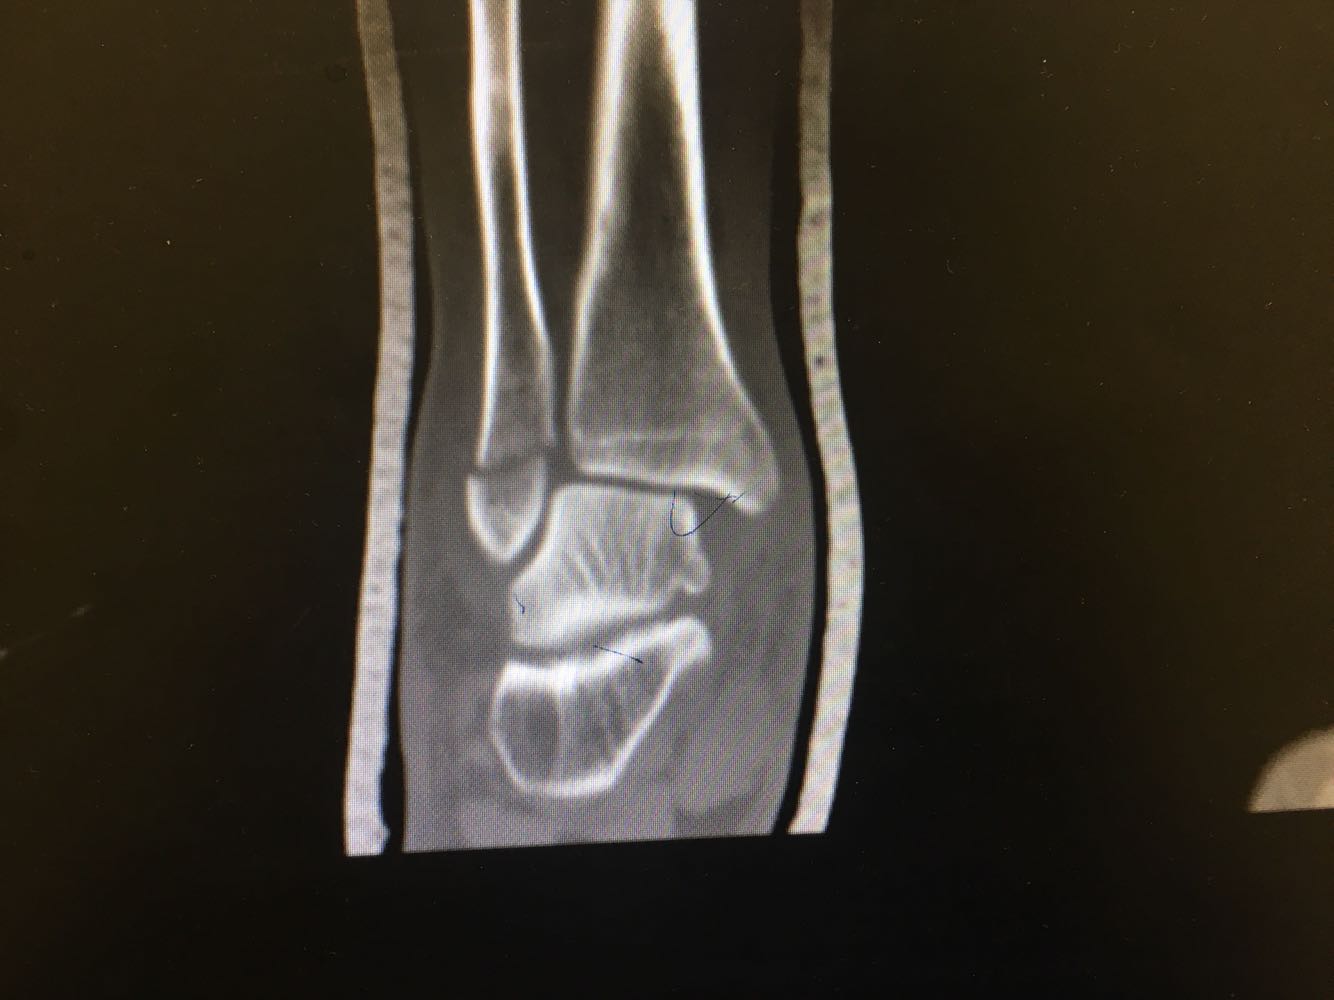

患者,男,54岁。 主诉:外伤致右踝疼痛伴活动受限2天 现病史:患者于2天前不慎扭伤致右踝疼痛,伴活动受限,否认头晕头痛、恶心呕吐等不适,就近医院就诊,查X片示:右踝骨折,予石膏外固定,现为进一步诊治收治入院,发病以来,神清,精神可,胃纳夜眠可,二便无殊,体重无明显变化。

查体:右踝压痛,活动受限,无淤斑淤点,未见皮肤破损,足趾感觉及运动良好。 辅检:右踝部CT

诊断:右侧踝部闭合性骨折 治疗:完善术前检查后行手术内固定